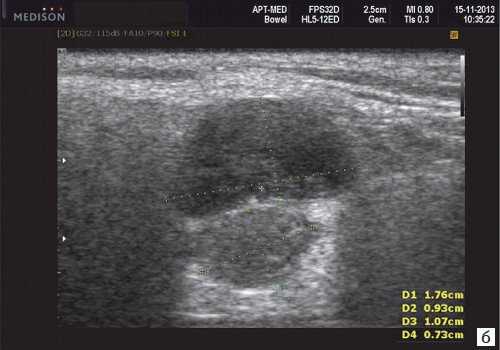

Рис. 9. Кисты слюнных желез.

- Кисты слюнных желез (мукоцеле). Различают два типа мукоцеле СЖ: ретенционный тип (ретенционная киста малой СЖ, формирующаяся при задержке слюны в выводном протоке) и тип внутритканевой секреции, когда при травме стенки протока слюна поступает непосредственно в волокнистую ткань, окружающую железу. Мукоцеле дна полости рта называются также ранулами.

- Кисты выводных протоков больших СЖ - выраженная дилатация выводного протока вследствие задержки в нем секрета. Блокада оттока слюны может быть вызвана различными причинами: опухолью, камнем, уплотнившейся слизью, поствоспалительным стенозом вплоть до рубцовой облитерации просвета.